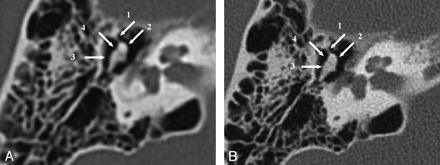

Temporal bone axial MPR, section thickness 0.8 mm, in both SST (A) and MSCT (B). The stapes crura (arrow) can be seen clearly with both imaging techniques.

Facial nerve canal axial MPR, section thickness 0.8 mm, in both SST (A) and MSCT (B). The geniculate ganglion (1), labyrinthine segment (2), and the tympanic segment (3) of the facial nerve can be seen in diagnostic quality with both imaging techniques. Note the status postmastoidectomy.